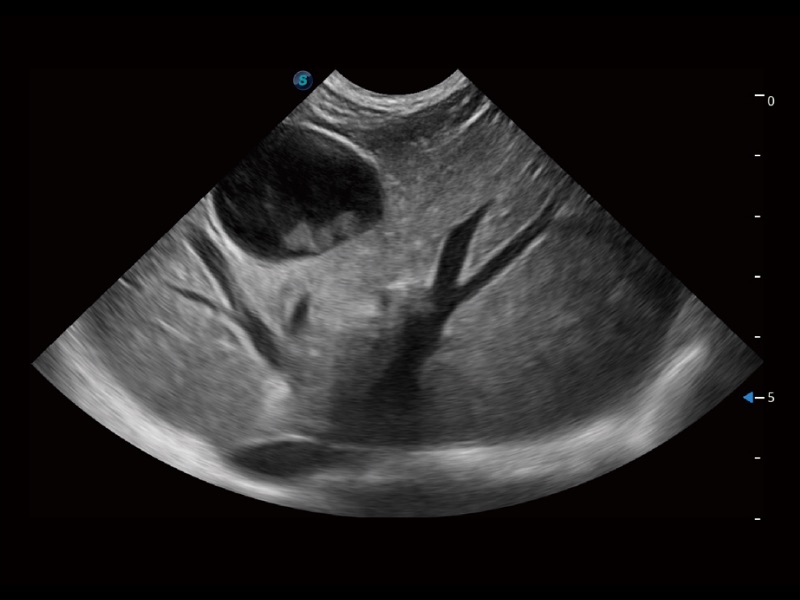

一鍵自動(dòng)識(shí)別膀胱壁及自動(dòng)測(cè)量膀胱容積,不受膀胱形狀和大小的限制,幫助醫(yī)生快速精準(zhǔn)獲得測(cè)量的數(shù)據(jù)。